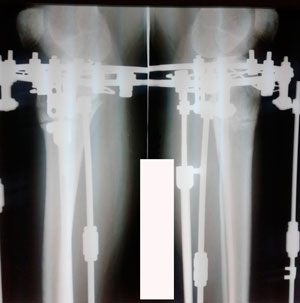

перед крутками

Вложения

image-27-03-20-03-47-1.jpg